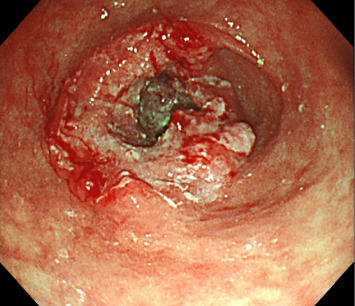

背景:人表皮生长因子受体2 (HER2)阳性胃癌约占胃癌病例的15%。曲妥珠单抗(Trz)是一种靶向HER2的单克隆抗体,已被证明与化疗联合可提高总生存率。然而,虽然trz诱导的心脏毒性(TIC)是乳腺癌化疗中公认的不良反应,但关于其在胃癌治疗中的发生的报道仍然有限。病例介绍:一名80岁日本男性her2阳性晚期胃癌(ciii期)患者在术后使用Trz + SOX方案(Trz、奥沙利铂和TS-1)化疗时出现室性心律失常和心力衰竭。患者最初因贫血和幽门狭窄行远端胃切除术并D1+淋巴结切除术。转移到#8a淋巴结(肝总动脉前上淋巴结)和通过淋巴结侵入胰腺的患者采用两个周期的Trz + SOX方案治疗,导致部分缓解。然而,在第11个周期后,他出现室性心动过速和心力衰竭。心脏影像学和实验室检查未发现冠状动脉病变或结构异常,提示TIC是根本原因。药物抗心律失常治疗导致症状缓解,无心律失常或心力衰竭复发。讨论:本病例强调了以非蒽环类药物为基础的Trz治疗胃癌的潜在心脏毒性。病理生理学上,HER2信号抑制可能会损害心肌细胞的应激反应和修复机制。患者的高龄、高血压和贫血史以及长期接受化疗可能是心脏易感性增加的原因。仔细监测心功能对于接受trz为基础的胃癌治疗的老年和合并症患者至关重要,以减轻心脏毒性的风险。结论:以trz为基础的化疗治疗her2阳性胃癌,即使不使用蒽环类药物,也可能造成心脏毒性的风险,特别是在老年人或合并症患者中。需要进一步的研究来阐明潜在的机制,优化这一人群的监测和预防策略。

Background: Human epidermal growth factor receptor 2 (HER2)-positive gastric cancer accounts for approximately 15% of gastric cancer cases. Trastuzumab (Trz), a monoclonal antibody targeting HER2, has been shown to improve overall survival when combined with chemotherapy. However, while Trz-induced cardiotoxicity (TIC) is a well-recognized adverse effect in breast cancer chemotherapy, reports on its occurrence in gastric cancer treatment remain limited. Case Presentation: An 80-year-old Japanese male with HER2-positive advanced gastric cancer (cStage III) developed ventricular arrhythmia and heart failure during postoperative chemotherapy with the Trz + SOX regimen (Trz, oxaliplatin, and TS-1). The patient initially underwent distal gastrectomy with D1+ lymphadenectomy for anemia and pyloric stenosis. Metastasis to the #8a lymph node (anterior superior lymph node of the common hepatic artery) and pancreatic invasion via lymph nodes were treated with two cycles of the Trz + SOX regimen, leading to a partial response. However, after the 11th cycle, he developed ventricular tachycardia and heart failure. Cardiac imaging and laboratory findings revealed no coronary artery disease or structural abnormalities, suggesting TIC as the underlying cause. Antiarrhythmic therapy with pharmacological agents led to symptom resolution, and no recurrence of arrhythmia or heart failure was observed. Discussion: This case highlights the potential cardiotoxicity associated with nonanthracycline-based Trz regimens for gastric cancer. Pathophysiologically, HER2 signaling inhibition in cardiomyocytes may impair stress responses and repair mechanisms. The patient's advanced age, history of hypertension and anemia, and cumulative exposure to chemotherapy may have contributed to increased cardiac vulnerability. Careful monitoring of cardiac function is essential in elderly and comorbid patients undergoing Trz-based therapy for gastric cancer to mitigate the risk of cardiotoxicity. Conclusion: Trz-based chemotherapy for HER2-positive gastric cancer, even without anthracyclines, may pose a risk of cardiotoxicity, particularly in elderly or comorbid patients. Further research is warranted to elucidate underlying mechanisms and optimize monitoring and prevention strategies in this population.